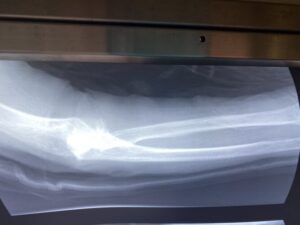

春日部市市民活動センター(前腕骨骨幹部骨折)

第26回整骨研究会「賜恩」研修会開催